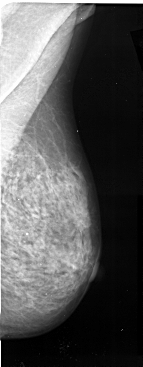

A_1025_1.LEFT_MLO

LEFT_MLO LINES 5506 PIXELS_PER_LINE 2146 BITS_PER_PIXEL 16 RESOLUTION 42 OVERLAY